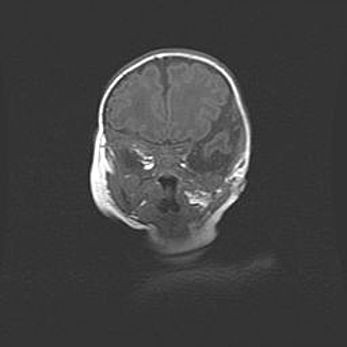

Церебральная ишемия II.

Возраст: 5 дней

Вес: 3400 г

Пол: женский

Окружность головы: 35 см

Срок гестации: 39 недель

Церебральная ишемия – это заболевание, характеризующееся недостаточностью (гипоксией) либо полным прекращением (аноксией) снабжения мозга кислородом по причине закупорки одного или нескольких сосудов. Это приводит к  что метаболическим расстройствам различной степени тяжести в тканях головного мозга, развитию коагуляционных некрозов и гибели нейронов.